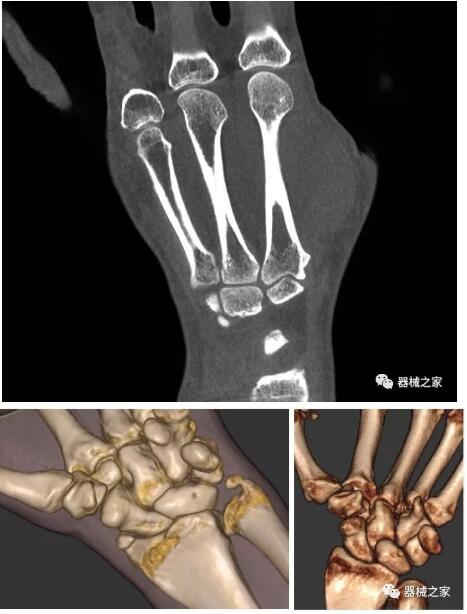

以下是這些“特立獨(dú)行”的CT所拍出來的圖像: